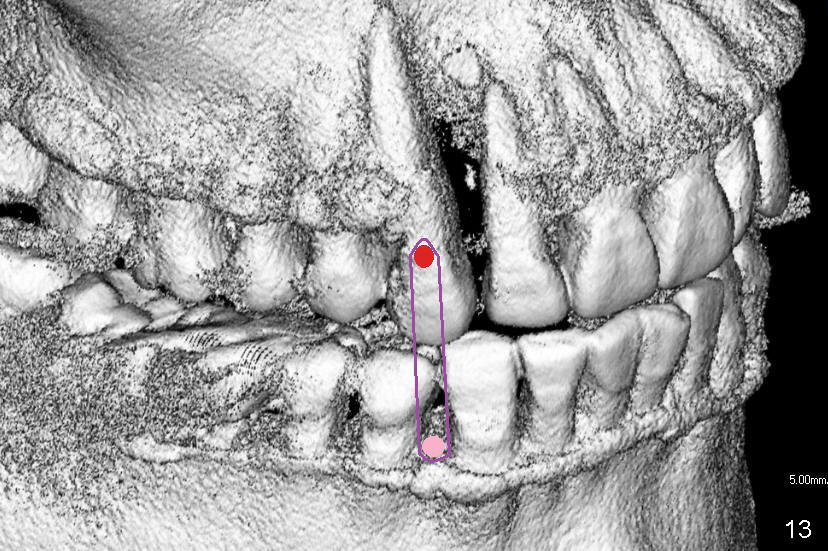

Treatment plan is to extrude #6 by placing a mini-implant between #27 and 28 (Fig.11-13) until the fracture line is exposed and the chronic infection is controlled.  The most importantly, the extrusion is expected to bring down the mesial papilla and the alveolar bone.  If the remaining root is not stable, the tooth is extracted and replaced by an implant.